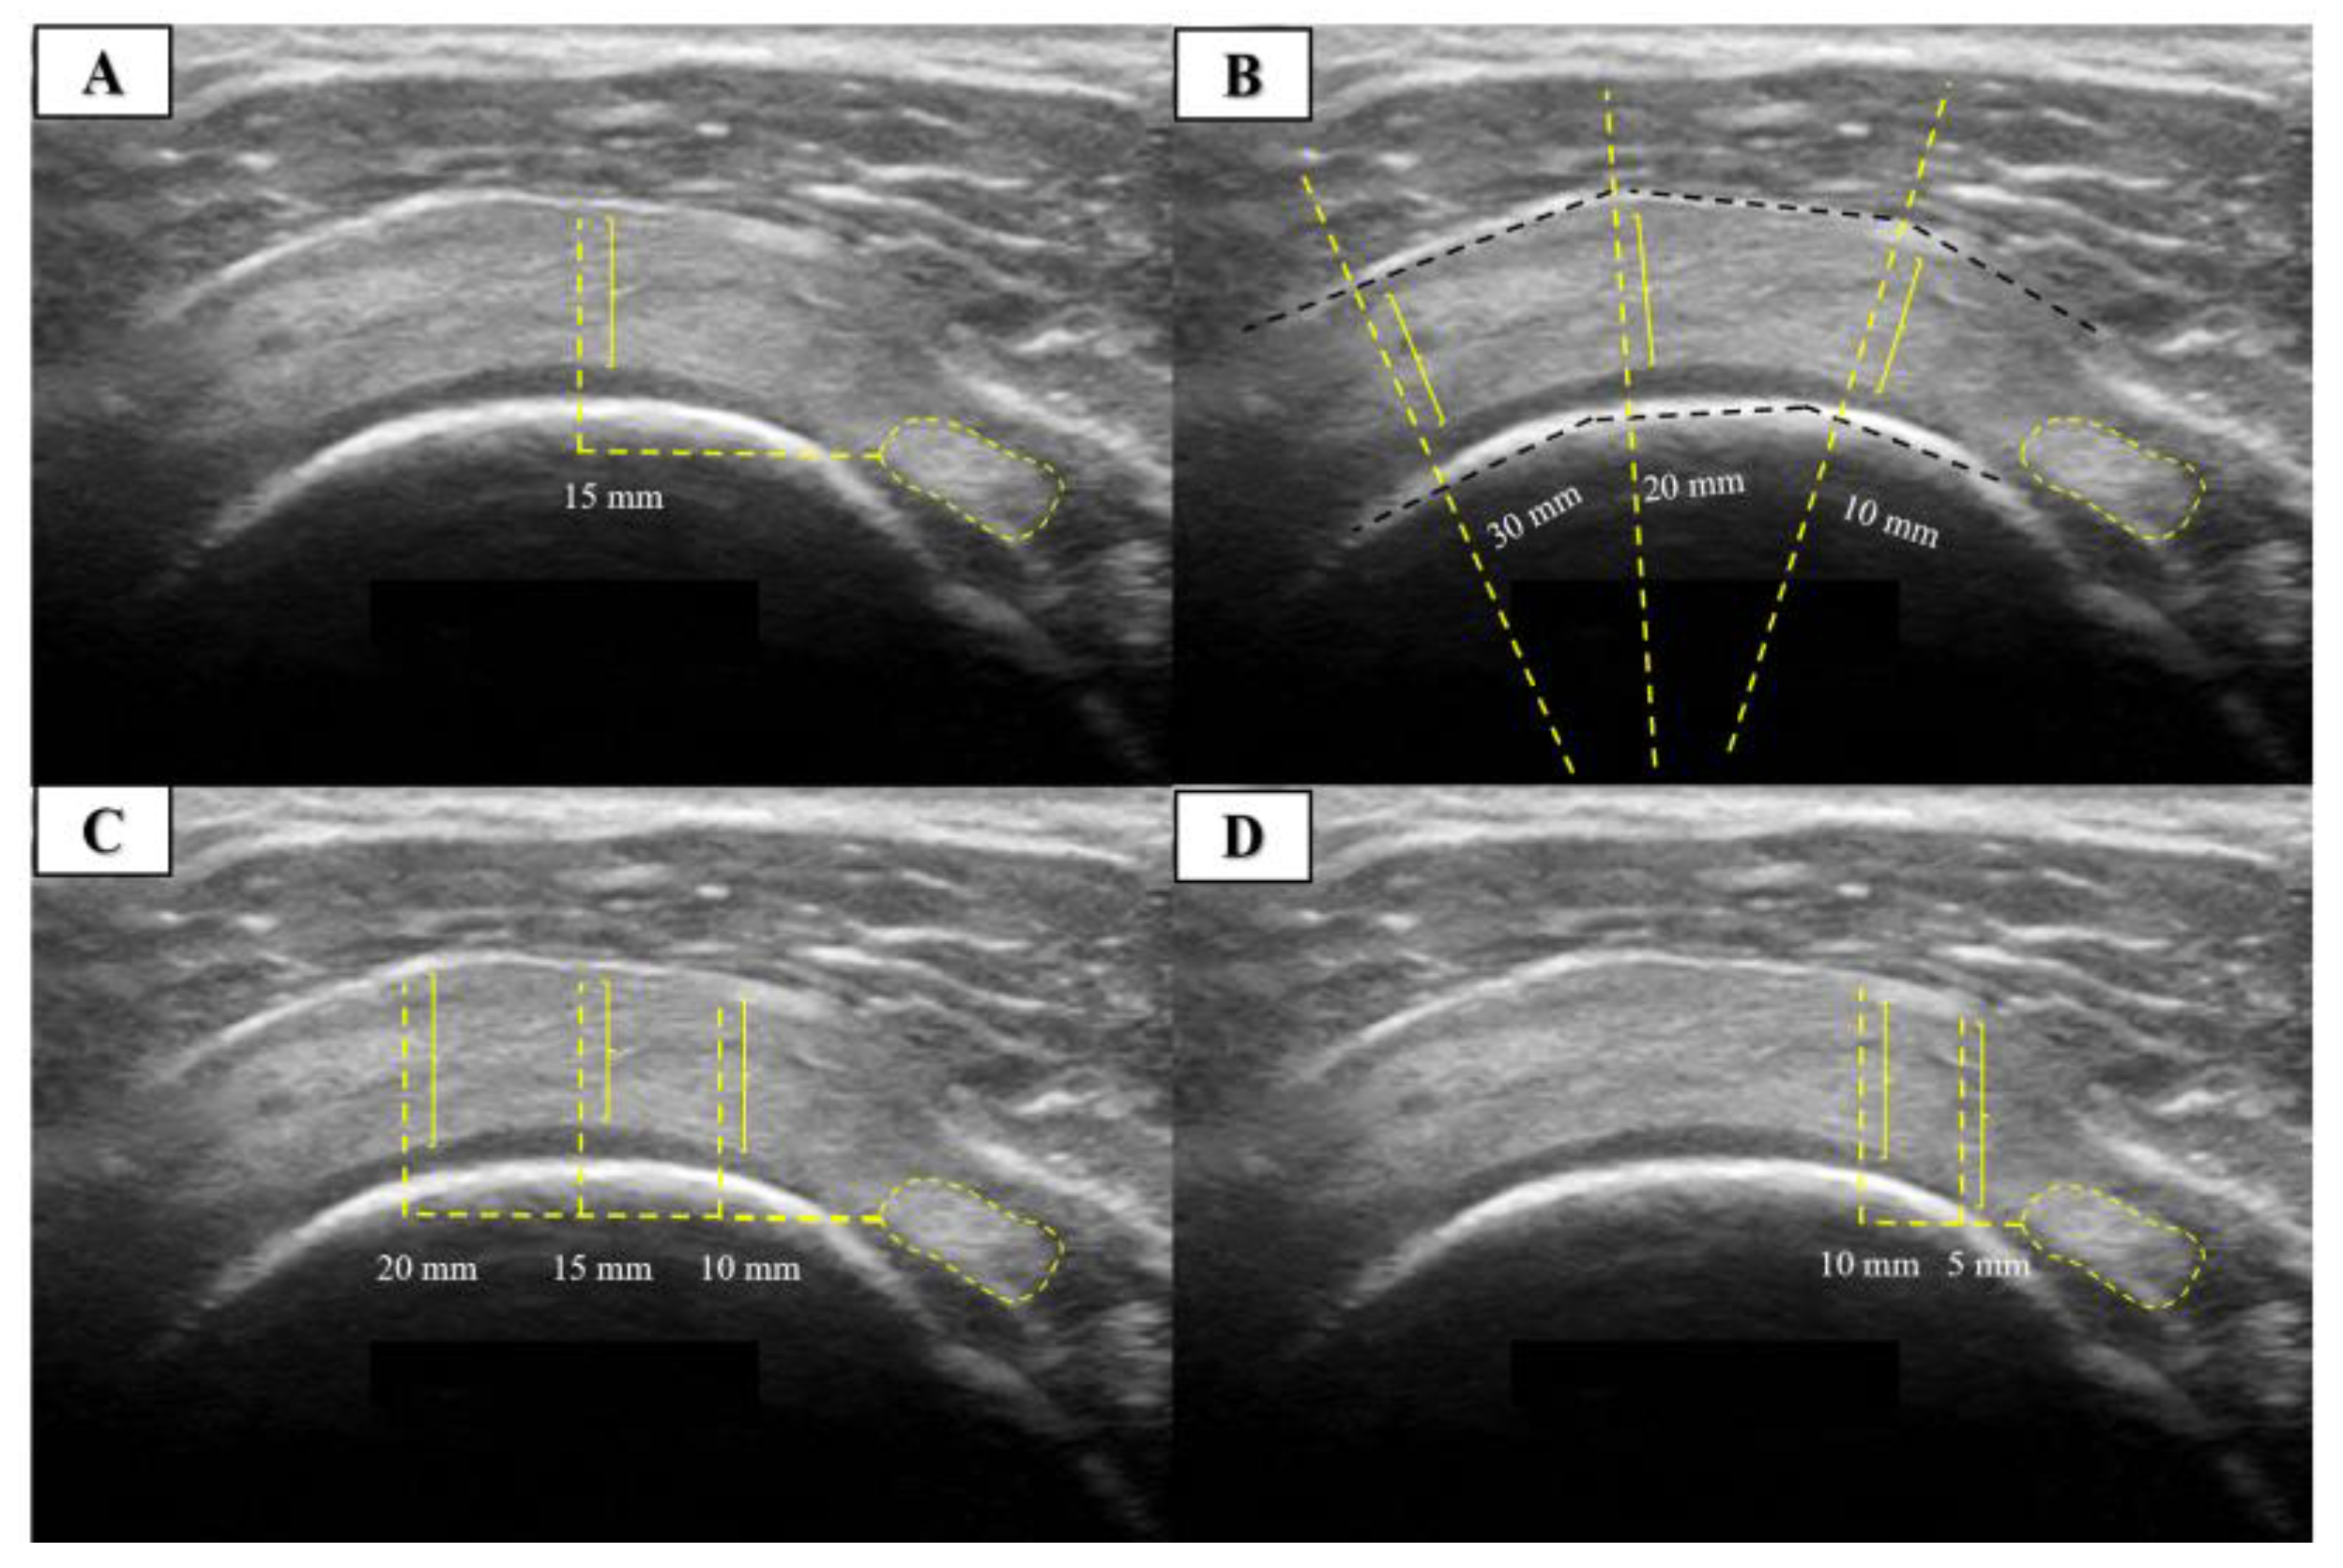

The measurement procedure for SST thickness consisted of four different measurement procedures performed and published over the last decade. The first measurement procedure took measurements at 15 mm [5], the second at 10, 20, and 30 mm [13], the third at 10, 15, and 20 mm [6], and the fourth at 5 and 10 mm [4] lateral to the most hyperechogenic reference point of the biceps tendon. All measurement procedures contained more than a single reference point that was averaged. An illustrative example of US images is shown in Figure 2.

Figure 2.

Ultrasound measurement of the supraspinatus tendon thickness in short axis. (A) Measurements were taken at 15 mm [5], (B) at 10, 20 and 30 mm [13], (C) at 10, 15 and 20 mm [6], and (D) at 5 and 10 mm [4] lateral to the most hyperechogenic reference point of the biceps tendon.